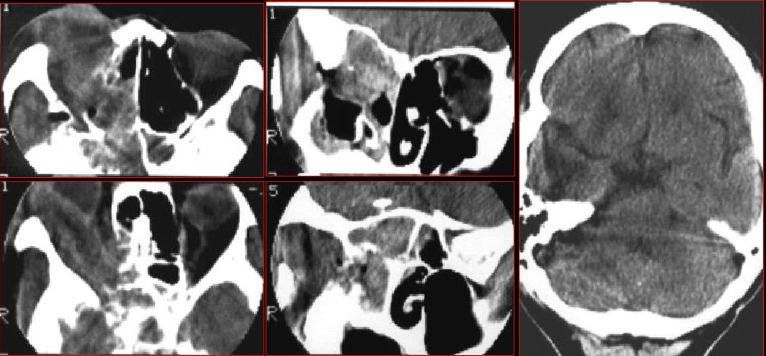

急性鼻窦炎

筛窦异物伴急性感染